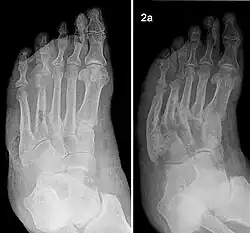

Charcot-Fuß bei Diabetes, Röntgenbilder im Verlauf. Links: Befall des 4. Zehengrundgelenks (Eichenholtz-Stadium I). Rechts: Nach 2 Jahren Zerstörung des 4. und 5. Zehengrundgelenks und totale Verknöcherung und Deformierung der Fußwurzel-Mittelfuß-Gelenke (Eichenholtz-Stadium III)

Der Charcot-Fuß kann nach verschiedenen Kriterien eingeteilt werden: nach Schweregrad und Aktivitätsstadium (Einteilung nach Chantelau und Grützner), nach dem Befall der Skelettanteile (Einteilung nach Sanders und Frykberg)[14] und nach dem röntgenologischen Verlauf (Einteilung nach Eichenholtz und Levin).